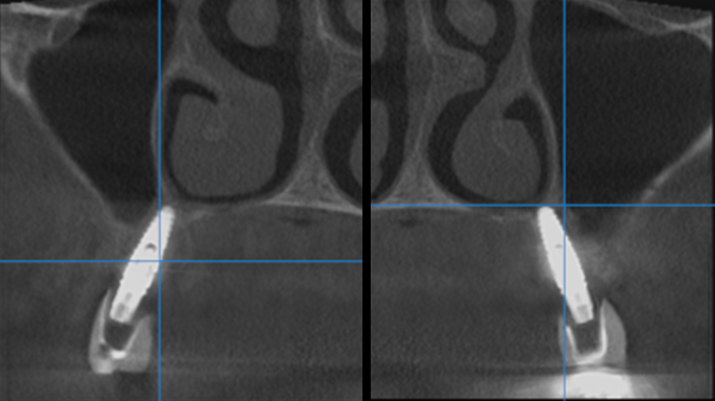

Clinical case: Extraction of all teeth in upper maxilla,

immediate implant placement, & provisionalization

- Courtesy of Dr. Iulian Filipov, Romania -

Keywords

AnyRidge, immediate placement, immediate provisionalization, maxillary fully edentulous case, initial stability, edentulous, Dr. Iulian Filipov, R2GATE, MEGA ISQ

Products:

AnyRidge implant system, Mega ISQ, R2GATE